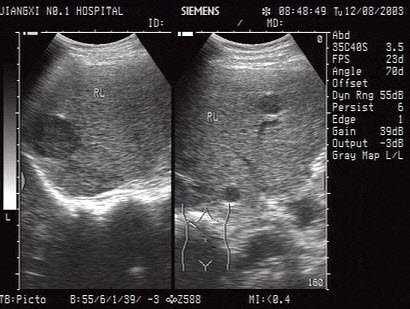

15、单项选择题

某患者,男,45岁,肝区不适,肝功能异常。行超声检查如图,诊断为()

A.弥漫性肝癌

B.结节状肝硬化

C.多发性血管瘤

D.血吸虫肝

E.不均匀性脂肪肝